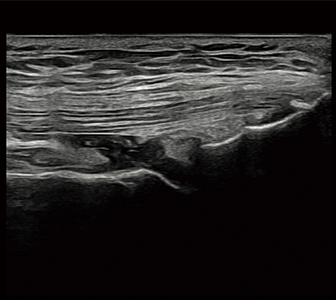

不明瞭部分をクリアに。